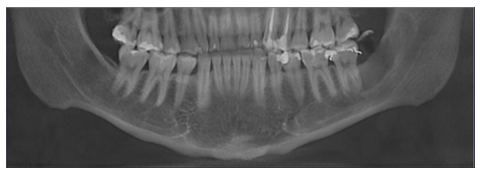

Se apreció en la ortopantomografía imagen pseudo radiolúcida localizada en el límite posterior del cuerpo mandibular, que se extendía desde las raíces de UD 37 hasta tercio medio de rama mandibular ipsilateral de bordes definidos, desplazando el conducto alveolar inferior y sin afectar la basal mandibular.

Figura 2 Detalle de Radiografía Panorámica que evidencia imagen pseudo radiolúcida unilocular de bordes corticalizados que se extiende en sentido cefálico caudal desde borde anterior de la rama y parte del reborde alveolar hasta la cortical del conducto mandibular izquierdo, se evidencia relación de la lesión con raíces de la UD 37. Fuente: Historia Clínica. Especialización Cirugía Bucal ULAC-IDOLA. 2022.

En la Tc Cone Beam en una vista oblicua se visualizó imagen unilocular hipodensa de bordes corticalizados compatible con lesión quística (Figura 3).

Figura 3 Corte de tomografía computarizada de haz cónico, en donde se evidencia en vista oblicua una imagen hipodensa compatible con la lesión, donde se observa desplazamiento del nervio dentario hacia la basal mandibular. Fuente: Historia Clínica. Especialización Cirugía Bucal ULAC-IDOLA. 2022.

Figura 4 Reconstrucciones multiplanares de tomografía computarizada de haz cónico, con vista oblicua (A) y medidas referenciales de 13.6 mm x 35.3 mm. Vista coronal (B) con imagen Hipodensa compatible con la lesión y una imagen hiperdensa compatible con la raíz distal de UD 37. En el corte axial (C) se evidencia ligera expansión de la cortical vestibular. Fuente: Historia Clínica. Especialización Cirugía Bucal ULAC-IDOLA. 2022.